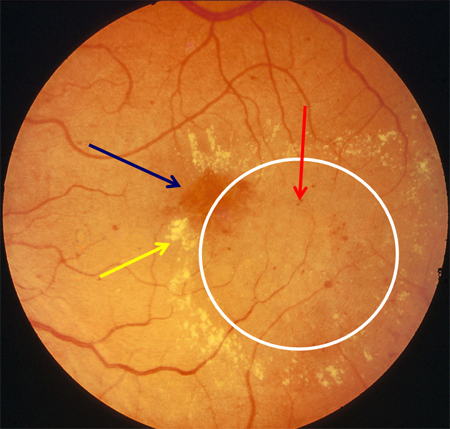

Non-proliferative diabetic retinopathy with macular oedema: exudate (yellow arrow)

Courtesy of Moorfields Photographic Archive; used with permission